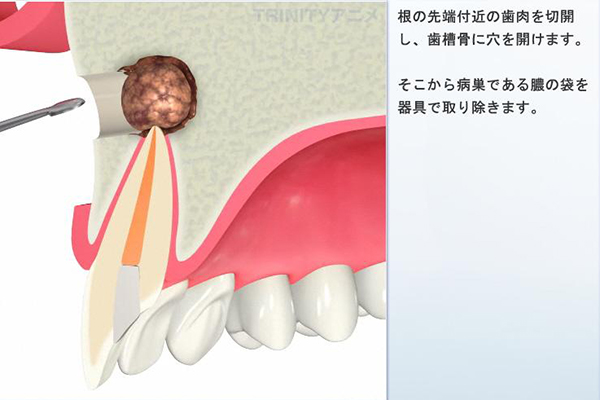

2.歯根端切除術

病変と根の先を切除する手術を行います。

メリット

- 意図的再植と異なり、歯を抜く必要がありません。

デメリット

- 骨の厚みや神経の位置関係によっては適応外となることがあります。

- 狭い範囲での処置になるため、感染物を取り残す恐れがあります。

- 術後に腫れや痛みを伴います。